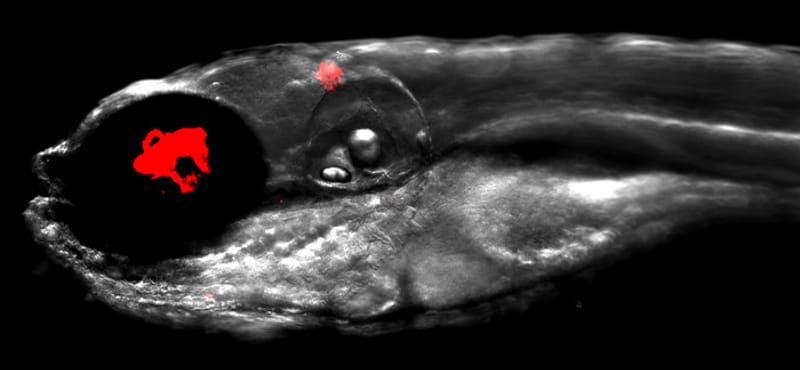

Baktériumölő vírusokkal (bakteriofágokkal) kombinált antibiotikumok adhatnak reményt a jövőben súlyos betegségek gyógyítására.

Baktériumölő vírusokkal (bakteriofágokkal) kombinált antibiotikumok adhatnak reményt a jövőben súlyos betegségek gyógyítására.